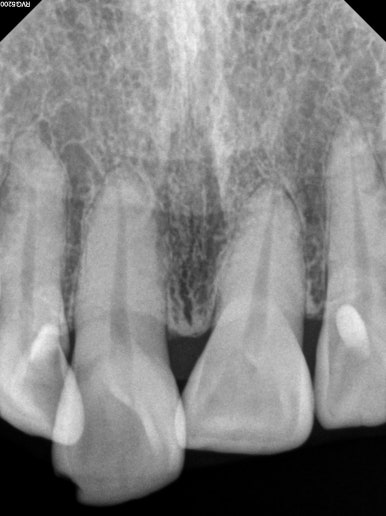

엑스레이를 찍는 이유는 잇몸이 건강한지를 확인하기 위함입니다.

50대 여성분임에도 불구하고 충분히 건강한 잇몸상태를 확인할 수 있었습니다.

그러면.. 교정치료가 가능하다는 뜻입니다.

치아의 뿌리 상태를 확인하기 위한 방사선 사진 촬영 필수!

교정을 하기 전에 무조건 위아래 앞니의 뿌리길이를 체크해야 합니다.

아무래도.. 성인교정의 대부분은 삐뚤어진 앞니 배열의 개선이지요?

그러면 앞니의 움직임이 다소 많을 것이기 때문에, 교정하기에 적합한 뿌리 길이를 갖고 있는지 확인해야합니다.

그런 면에서 이번 환자분은 당연히 합격!